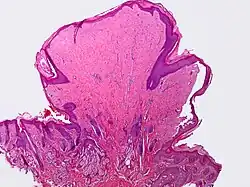

A skin tag, or acrochordon (pl.: acrochorda), is a small benign tumor that forms primarily in areas where the skin forms creases (or rubs together), such as the neck, armpit and groin. They may also occur on the face, usually on the eyelids. Though tags up to 13 mm (1⁄2 inch) long have been seen,[2] they are typically the size of a grain of rice. The surface of an acrochordon may be smooth or irregular in appearance and is often raised from the surface of the skin on a fleshy stalk called a peduncle. Microscopically, an acrochordon consists of a fibrovascular core, sometimes also with fat cells, covered by an unremarkable epidermis. However, tags may become irritated by shaving, clothing, jewelry, or dermatitis.